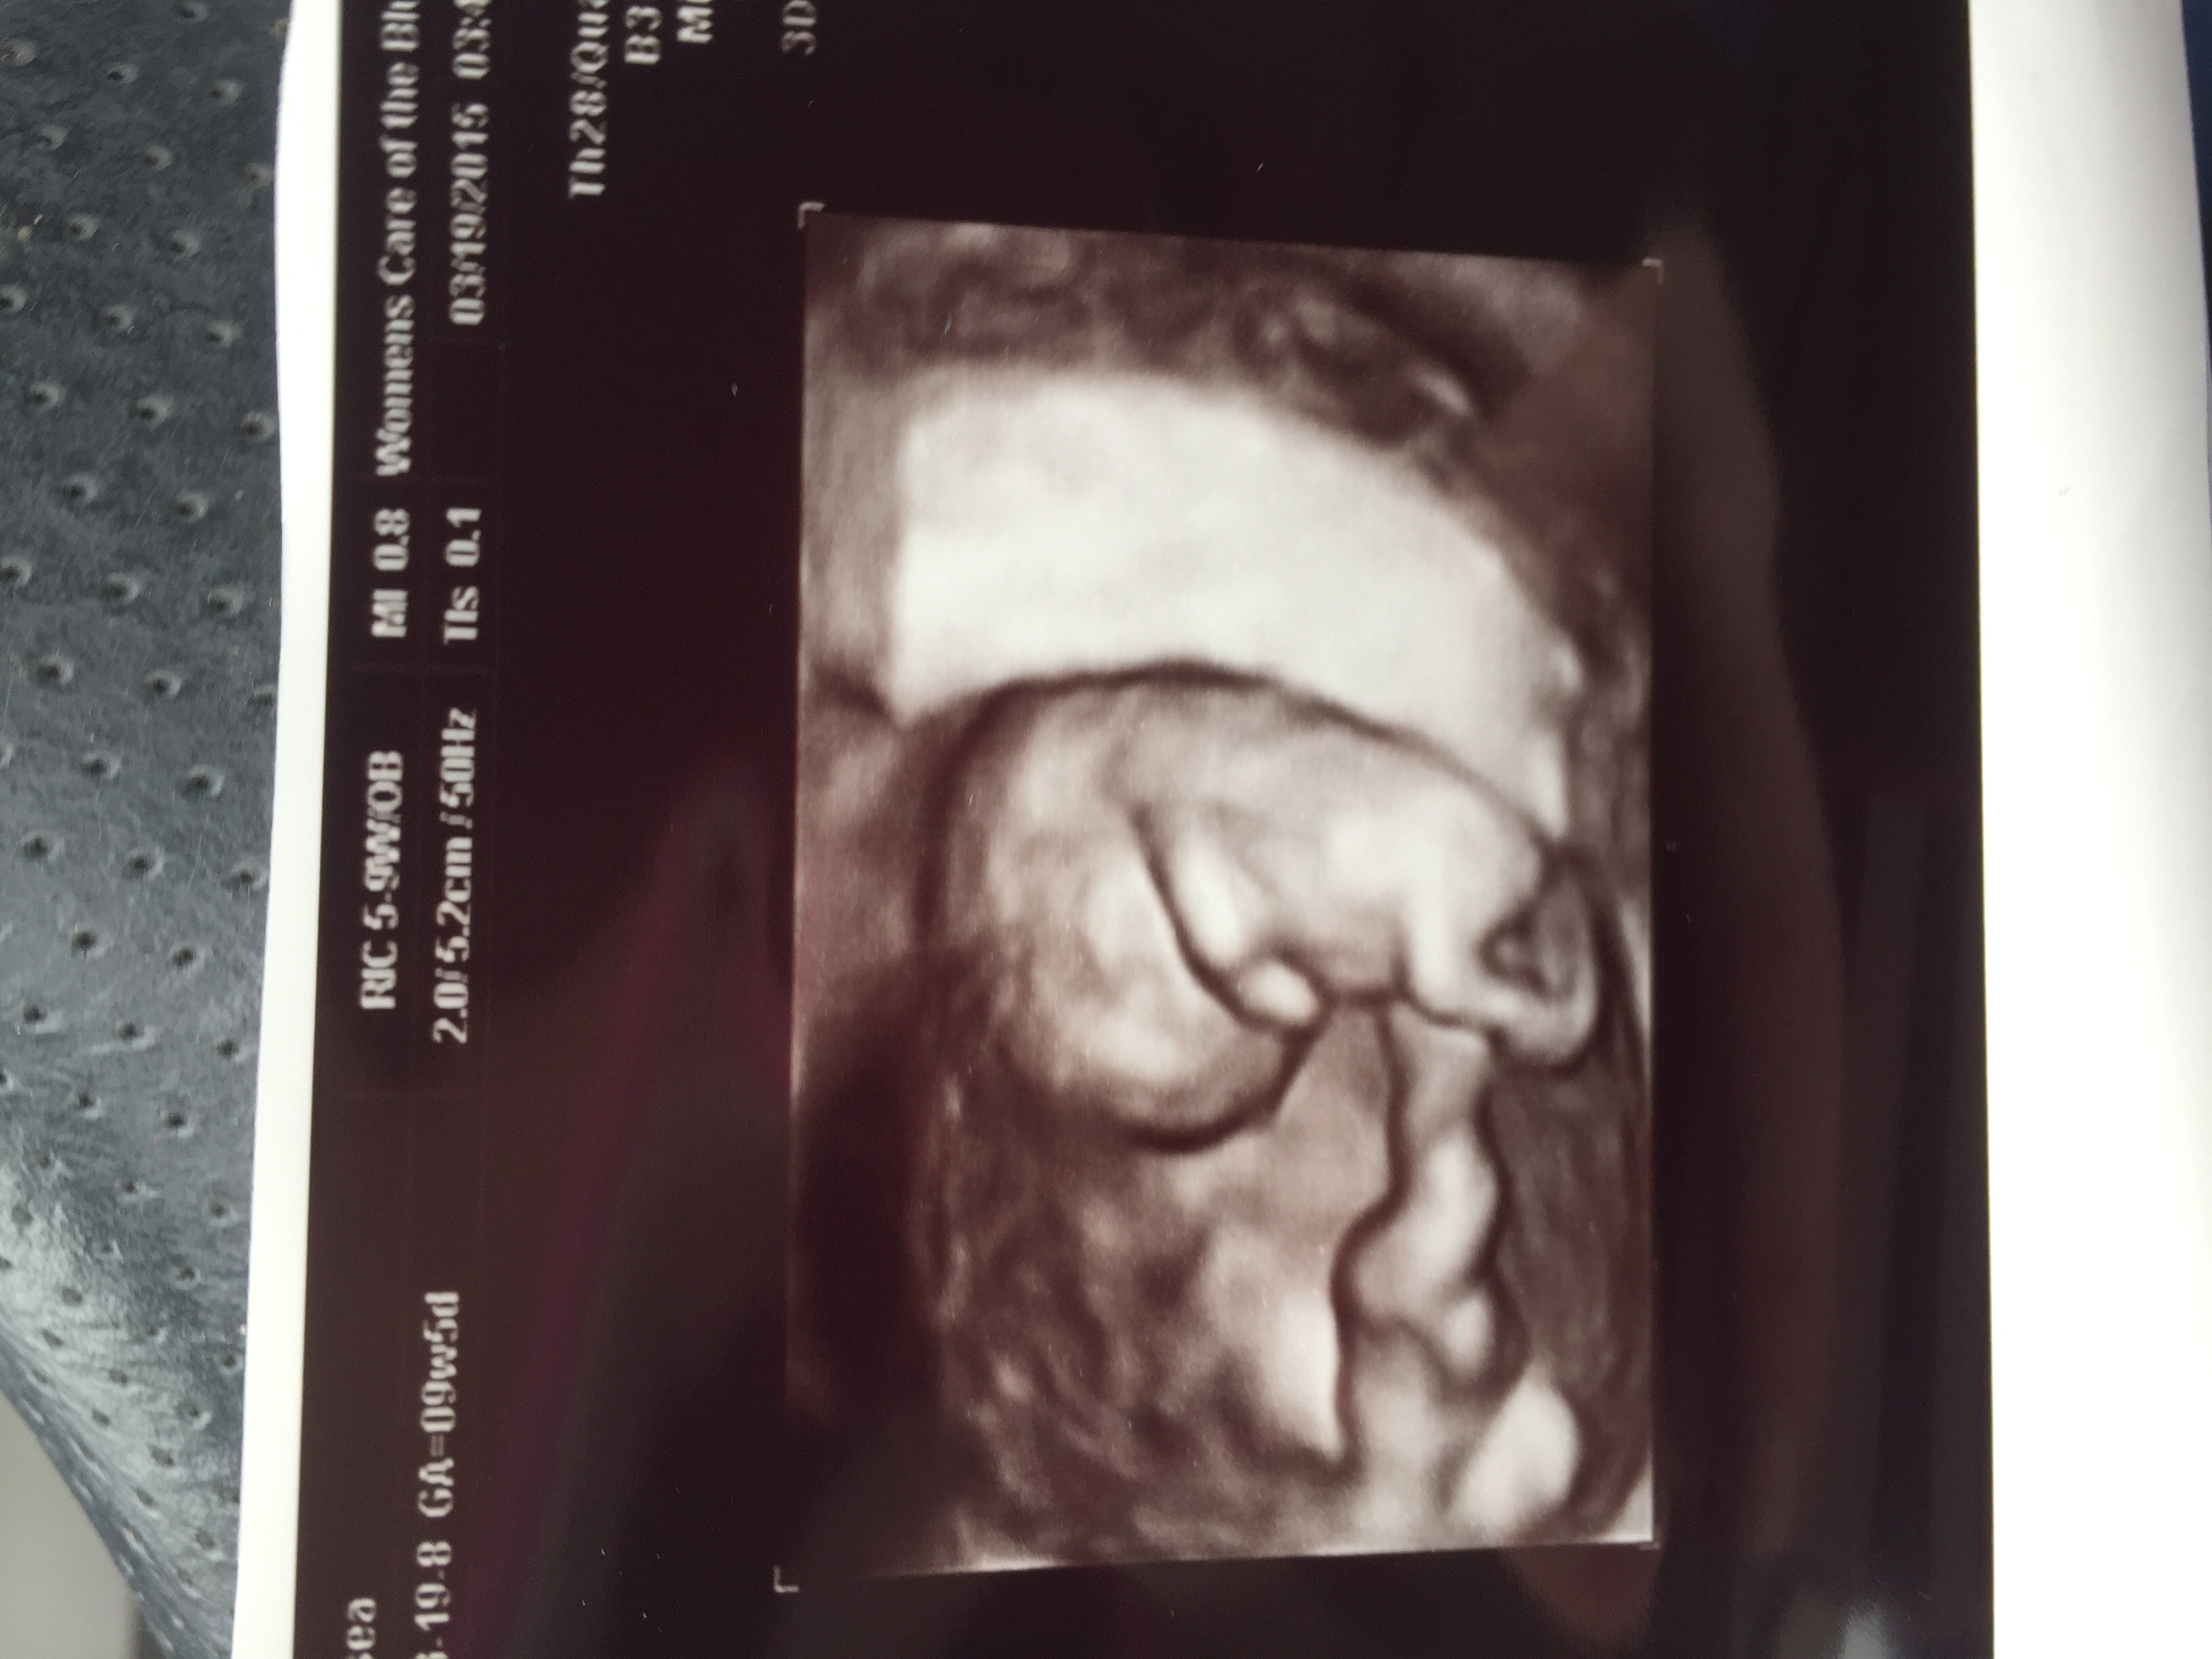

Got a surprise ultrasound today at 14w1d- thought we were just going to hear the heartbeat but we got pics too! Last time was at 9 weeks and she looked like a white smear on the U/S. Now look! So exciting!!